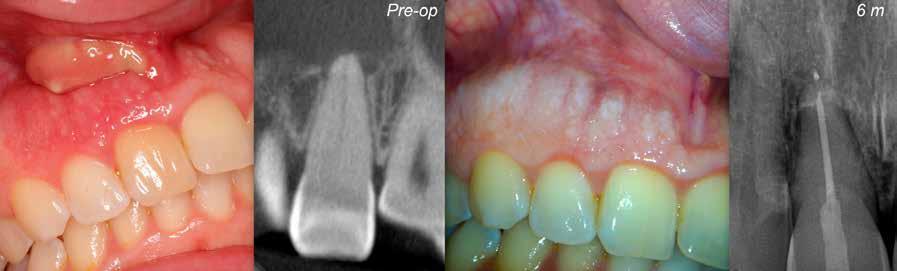

Diagnózis és kezelési lehetőségek

A nyaki harmadban kialakult külső gyökérfelszívódás pontos etiológiai háttere a mai napig tisztázatlan. Vélelmezhetően multifaktoriális okok állnak a kialakulása hátterében, amely a dentin fognyaki régióban történő szabaddá válásához vezet. Ez a folyamat a saját természetes fogak mintegy 10%-át érinti. Az exponálódott dentin ennek következtében kapcsolatba kerül az oszteoclast sejtekkel, amelyek a foganyag leépülését okozzák. Ebben a cikkben egy olyan klinikai eset kerül bemutatásra, amelyben egy krónikus periapikális lézióval és Class III. külső fognyaki gyökérfelszívódással rendelkező fog kezelését végeztük. Az ellátás során a fogat sebészi módszerekkel szándékosan eltávolítottuk, majd a szájüregen kívül rezekáltuk és a reszorbcióval érintett területet is kezeltük, ezt követően pedig replantáltuk.

A 38 éves hölgy páciens a jobb alsó második kisőrlőfog területéről (45) eredő fájdalom miatt kereste fel rendelőnket. A panaszai rágás közben fokozódtak. A páciens általános anamnézisében nem szerepelt semmi kiemelendő. Elmondása szerint a bal alsó kisőrlőfogát korábban gyökérkezelték, valamint 7 évvel ezelőtt fogszabályzó kezelésben részesült. A klinikai vizsgálat során a kérdéses fognál kopogtatási érzékenységet regisztráltunk, illetve a fog disztoapproximális felszínének megfelelően több mint 3 mm-es tasakmélységet mértünk.

A radiológiai felvételek elemzése során a fog gyökércsúcsának megfelelően radiolucens elváltozást észleltünk, valamint a fognyak területének megfelelően szintén egy radiolucens területet figyelhettünk meg (1–2. ábra). Az elváltozások kiterjedésének és mélységének pontosabb meghatározása érdekében CBCT-felvétel készült (3. ábra). A felvétel alapján Heithersay-féle III. osztályú külső fognyaki gyökérfelszívódást diagnosztizáltunk (Heithersay Class III external cervical invasive root resorption; ECIR). Ezzel egyidejűleg pedig szimptomatikus periapikális periodontitis is fennállt. Ezt követően a pácienst a vizsgálati eredményekről, a kezelési alternatívákról és a várható prognózisról is tájékoztattuk.

Az ECIR következtében kialakult defektus ellátását Heithersay ajánlásainak megfelelően, de egy új kezelési alternatíva alkalmazásával végeztük. A kezelés során a fogat szándékosan eltávolítottuk és extraorálisan kezeltük (rezekció, reszorbció ellátása). Heithersay az ECIR okozta elváltozásokat négy kategóriába sorolta. Az I. és II. osztályba sorolt elváltozások kezelése során általában 100%-os sikerességre számíthatunk. Ezzel szemben a III. osztályú elváltozások esetében már csak 77%-os, míg a IV. osztályú lézióknál csupán 12%-os sike-

resség jellemző. Minél előrehaladottabb állapotban van a rezorptív lézió, annál roszszabb prognózisra és annál komplexebb kezelési igényre számíthatunk.

A periapikális léziók rezekciót követő gyógyulási hajlamát több faktor is befolyásolhatja. Ezek közül elsősorban a retrográd preparáció mélységét (amelynek minimum 3 mm-t el kell érnie) és a retrográd gyökértömés során felhasznált anyagot emelnénk ki. A beavatkozás óta eltelt idő is hatással van a gyógyulás aktuálisan megfigyelhető stádiumára. Minél hosszabb idő telt el a beavatkozás óta, potenciálisan annál teljesebb körű csontos telődésre számíthatunk. Ebben az esetben az obszervációs periódus során több CBCT-felvételt is készítettünk, hogy végig tudjuk követni a gyógyulás folyamatát. A kezelés során a fogat szándékosan eltávolítottuk, majd a rezorpciós üregben lévő granulációs szövetet kikürettáltuk és a megtisztított felszíneket 90%-os triklór-ecetsavval fertőtlenítettük. Az így előkészített üreget hidrofil tulajdonságokkal rendelkező dual kötésű nano-hibrid resintartalmú ionomer cementtel töltöttük fel (Geristore, DenMat; 4. ábra).

Ezt követően a gyökércsúcsot extraorálisan rezekáltuk, majd a gyökércsatornát retrográd irányból ultrahangos eszközök segítségével 3 mm mélységben feltágítottuk (EndoSuccess apikális sebészeti készlet, EndoSuccess apical surgery kit; ACTEON). A retrográd gyökértömést ásványi trioxid aggregátum (mineral trioxide aggregate, MTA) felhasználásával végeztük (CeraPutty, Meta Biomed), majd replantáltuk a fogat. A visszahelyezést követően szemi-rigid sín segítségével stabilizáltuk a fogat, amelyet 4 hét elteltével távolítottunk el (5. ábra). A beavatkozásokat követően 6 hónappal a gyógyulás ütemének ellenőrzése érdekében kontroll CBCT-felvételt készítettünk. A felvételen a terület maradéktalan regenerációja volt megfigyelhető, a periapikális lézió szinte teljes mértékben telődött (6. ábra). A szájüregi állapot is megfe-

4. a–b ábra: A sebészi fogeltávolítást követően végzett extraorális ellátás. A rezorpciós üreg kürettálását követően az esetlegesen visszamaradt lágyszövetek eltávolítására triklór-ecetsavba mártott vattagombócot használtunk (a), a kitisztított üreget Geristore-ral (DenMat) töltöttük fel (b).

lelőnek mutatkozott, illetve kontroll periapikális röntgen is készült, amely szintén megerősítette a CBCT felvételen látottakat (a korábban jelenlévő periapikális felritkulás csontos telődése) (7. ábra). A páciens teljes tünet- és panaszmentességről számolt be.

A kiindulási vizsgálat során talált eredmények közlését és a terápiás javaslat ismertetését követően a páciensben a saját fogának elvesztésével kapcsolatban merültek fel félelmek. A kezelési terv ismertetése során lépésről lépésre elmagyaráztuk az elvégezni kívánt beavatkozás menetét, azonban arra is felhívtuk a figyelmét, hogy a kezelés sikeressége nagymértékben a páciens gyógyulási hajlamától függ. A cél az volt, hogy a páciens kívánságainak megfelelően a saját természetes fogát a lehető leghosszabb ideig funkcióban megőrizhessük és elkerüljük, hogy a fog elvesztését követően implantátumot kelljen behelyezni. Azt is kifejtettük neki, hogy annak ellenére, hogy a fogeltávolítást követő replantáció sikeressége 90% körül van és a gyökér-

5. a–d. ábra: A gyökércsúcs-rezekciót és a retrográd preparálást extraorálisan végeztük. A retrográd üregalakítás során ultrahangos eszközöket alkalmaztunk (a–b), a retrográd gyökértömés CeraPutty-val (Meta Biomed) készült (c–d).

ábra: A 6 hónappal később készült kontroll CBCT-felvételen a periapikális lézió szinte teljes körű gyógyulása volt megfigyelhető.

ábra: A szintén 6 hónappal később készített kontroll röntgenfelvétel is a CBCT-felvételen látottakat erősítette meg.

csúcs-rezekció sikeressége is 80% körülire tehető, az elérhető eredményt elsősorban a parodontális rostokban lévő őssejtek regenerációs hajlama, a beavatkozás során használt anyagok, valamint ezeknek a bioaktív tulajdonságai határozzák meg.

Jelenleg is szakmai vita tárgyát képzi, hogy melyik a legideálisabb anyag a rezorpció által okozott üregek ellátására. Az ínnyel való biokompatibilitás, valamint a biológiai tulajdonságok tekintetében a CeraPutty és a Geristore dual kötésű nano-hibrid resintartalmú ionomer cement alkalmasnak

látszik a gyökérrezorpciók ellátására. Ezekkel az anyagokkal jó eredményeket lehet elérni. A Geristore mellett hosszú hámtapadás is ki tud alakulni, és ezen felül úgy tűnik, hogy a Geristore felszíne más anyagokhoz képest kedvezőbb plakkretentív tulajdonságokkal rendelkezik. A sebészi fogeltávolítást követően extraorálisan végzett rezektív beavatkozások sikeressége megfelelőnek látszik ahhoz, hogy a páciens számára jó eséllyel biztosíthassuk a fog hosszú távú megtarthatóságát. Ez egy olyan terápiás alternatíva, amely alkalmas lehet a periapikális lézióval rendelkező gyökérkezelt fogak oly módon történő ellátására, amely lehetővé teszi az egyébként elérhetetlen területeken lévő cervikális rezorptív léziók sikeres kezelését.